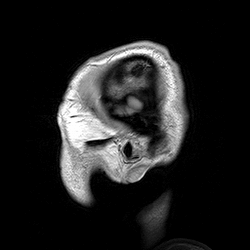

Магни́тно-резона́нсная томогра́фия (МРТ) — способ получения томографических медицинских изображений для исследования внутренних органов и тканей с использованием явления ядерного магнитного резонанса. Способ основан на измерении электромагнитного отклика атомных ядер, находящихся в сильном постоянном магнитном поле, в ответ на возбуждение их определённым сочетанием электромагнитных волн. В МРТ такими ядрами являются ядра атомов водорода, присутствующие в огромном количестве в человеческом теле в составе воды и других веществ[1].

Томография позволяет визуализировать с высоким качеством головной, спинной мозг и другие внутренние органы. Современные технологии МРТ делают возможным неинвазивно (без вмешательства) исследовать работу органов — измерять скорость кровотока, тока спинномозговой жидкости, определять уровень диффузии в тканях, видеть активацию коры головного мозга при функционировании органов, за которые отвечает данный участок коры (функциональная магнитно-резонансная томография — фМРТ).